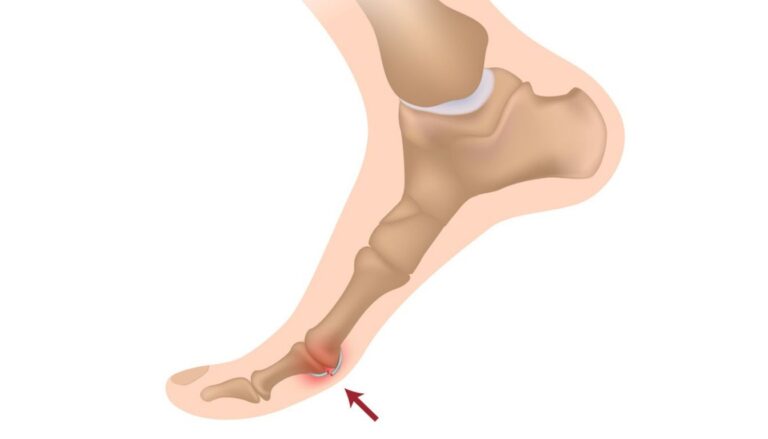

Czy kiedykolwiek zastanawiałeś się, dlaczego u niektórych osób występuje wystająca kość na stopie, a…